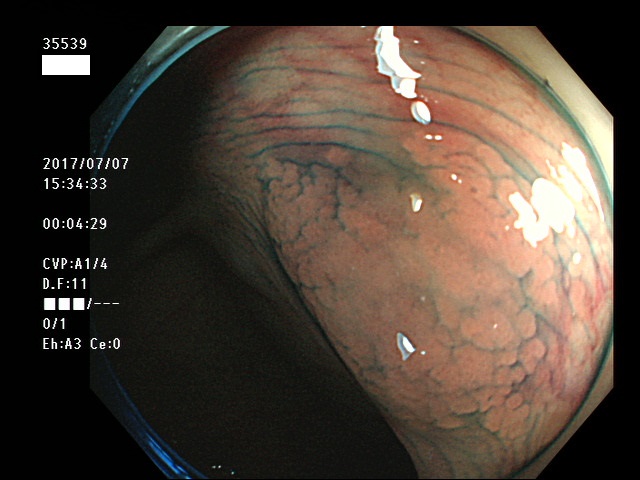

上記100名より抽出した平坦・陥凹型腺腫・SSAP(=癌化の危険が高いが見落としやすい病変)の内視鏡写真

35500 35501 35502 35506 35508 35509 35511 35514 35515 35516 35517 35520 35521 35522 35523 35524 35525 35526 35528 35532 35535 35536 35539 35542 35544 35545 35547 35548 35550 35553 35556 35559 35560 35561 35562 35563 35564 35567 35569 35570 35571 35578 35581 35584 35585 35587 35588 35589 35590 35592 35593 35594 35598 35599・・・・・の54名